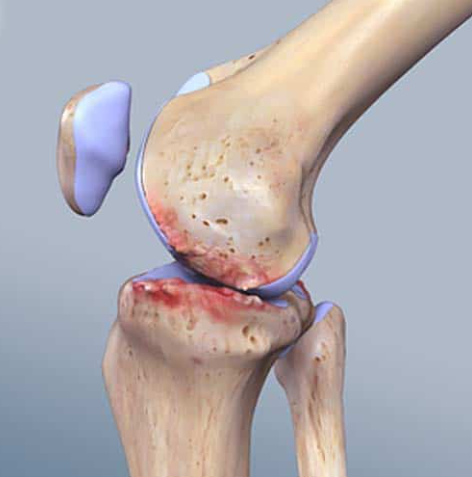

ข้อเข่าเสื่อม (Knee Osteoarthritis)

ข้อเข่าเสื่อม (Knee Osteoarthritis) คือภาวะที่กระดูกอ่อนผิวข้อสึกหรอ ตามอายุ การใช้งาน...